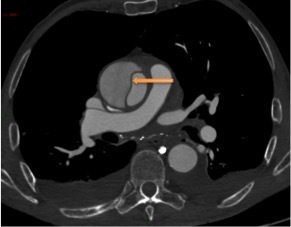

Un angioscanner thoraco-abdomino-pelvien est donc réalisé. Les Figures 11, 12, 13, 14 et 15 présentent des reformations axiales issues de celui-ci.

Question 7 : Concernant les structures légendées, quelles sont la/les proposition(s) exacte(s) ?

Vrai chenal

Déchirure intimale, qui constitue la porte d’entrée de la dissection.

Artère carotide commune droite

Artère coronaire droite naissant du sinus de Vasalva

Visualisation de la déchirure intimale d’où nait le faux chenal, dans lequel la déchirure est éversée, au niveau de l’aorte ascendante, avec un flap intimal étendu au tronc artériel brachio-céphalique, à la carotide commune droite et à la carotide commune gauche. En revanche absence d’extension au sinus de Vasalva, à la coronaire droite.

Dissection aortique de type A selon Stanford avec porte d’entrée de l’aorte ascendante en amont du tronc artériel brachio-céphalique et extension aux troncs artériels supra-aortiques. Pas d’extension au sinus de Vasalva, aux coronaires ni à l’aorte descendante. Pas de signe de rupture intra-péricardique ou intra-médiastinale.